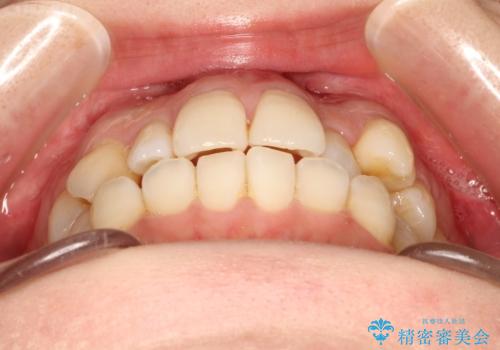

インビザラインで八重歯の矯正

- 八重歯を治したいとのことで、来院されました。

インビザラインにて、上顎の歯と歯の間をわずかに削り、並べる計画としました。

使用時間を守っていただけたので、比較的スムーズに矯正を終了することができました。